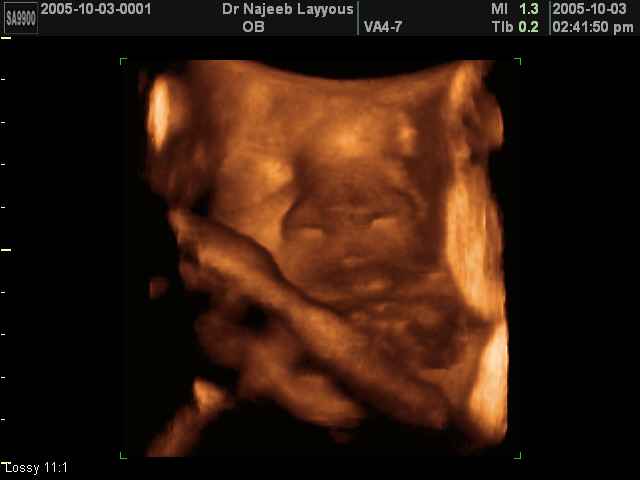

3D Photos échographie des parties du fœtus | Dr N Layyous

3D Photos échographie des parties du fœtus